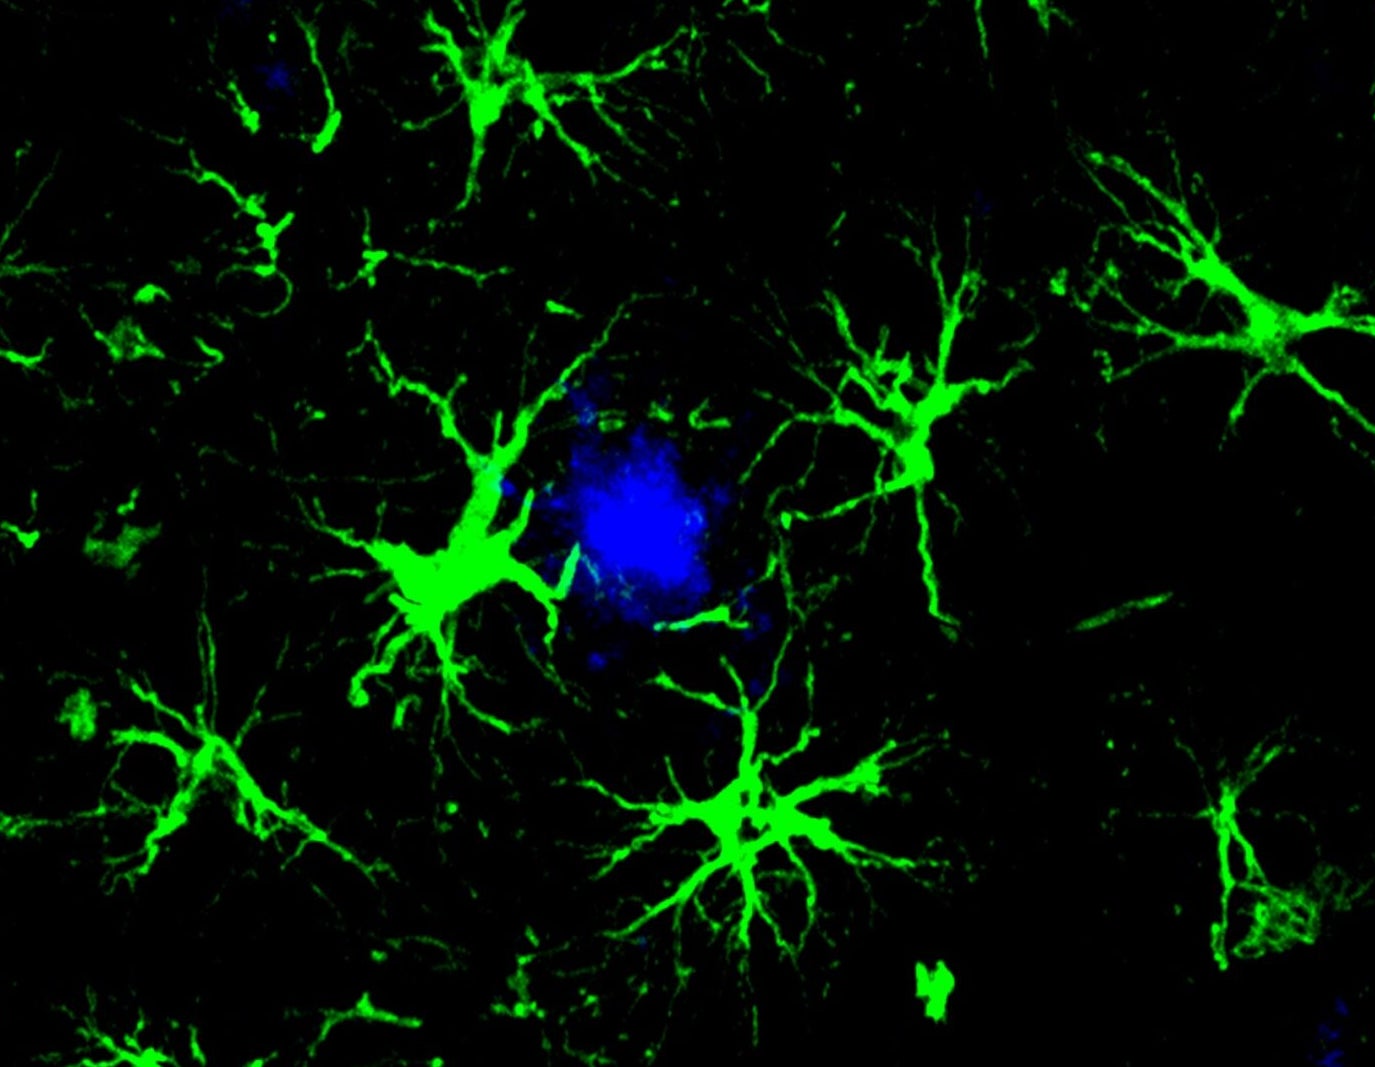

Ερευνητές στο Washington University μετέτρεψαν αστροκύτταρα — κύτταρα-υποστήριξης του εγκεφάλου — σε μηχανές καταστροφής της τοξικής αμυλοειδούς πρωτεΐνης που συνδέεται με τον Αλτσχάιμερ. Μία μόνο ένεση σε ποντίκια αρκούσε για να μειώσει τις τοξικές πλάκες κατά το ήμισυ. Η τεχνολογία δανείζεται από τις θεραπείες CAR T που έχουν φέρει επανάσταση στη θεραπεία του καρκίνου του αίματος.

Τώρα, μια ομάδα στο Washington University School of Medicine στο Σεντ Λούις δοκίμασε μια τελείως διαφορετική προσέγγιση, εμπνευσμένη από τις θεραπείες CAR T — μια τεχνολογία που γενετικά τροποποιεί τα Τ-κύτταρα του ανοσοποιητικού ώστε να εντοπίζουν και να καταστρέφουν καρκινικά κύτταρα. Αντί για Τ-κύτταρα, οι ερευνητές επέλεξαν τα αστροκύτταρα — κύτταρα του εγκεφάλου που υποστηρίζουν τους νευρώνες, βοηθούν στην επισκευή τραυματισμών και επηρεάζουν τη μνήμη και τη γνωστική λειτουργία. Τα τροποποίησαν γενετικά ώστε να αναγνωρίζουν και να καταβροχθίζουν την αμυλοειδή πρωτεΐνη, δημιουργώντας αυτό που ονόμασαν CAR-A κύτταρα.